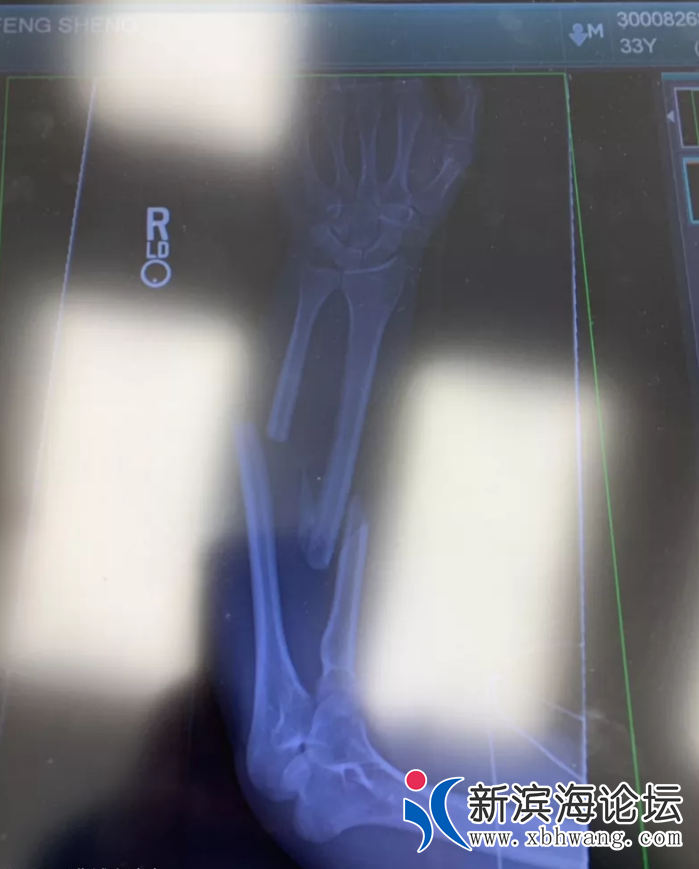

哎!娶了个母老虎回家,170斤的她把我摁在地上揍,手腕骨折了

娶了个母老虎回家,稍有不如意就对我横眉冷对,昨天打架直接把我摁在地上,羡慕人家恩爱的夫妻。真的怀疑她有易怒症,170斤的人把130斤的我摁在地上,我还有命吗?膀子骨折去医院拍片了。。。自己找的老婆只能自己受着了,哎,也只能来这发发牢骚了